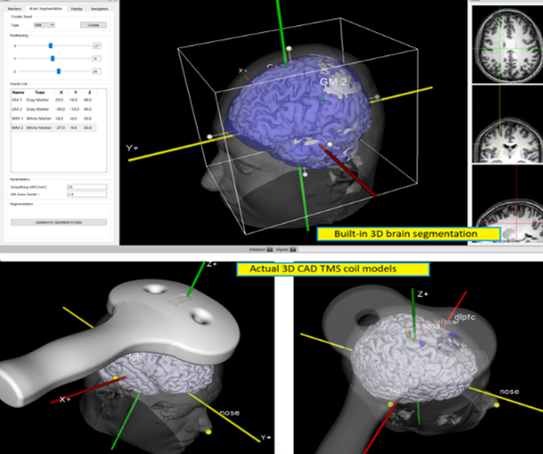

In addition to consultation, brain mapping, and digital cognitive exams, our team recommends either anatomical MRI or functional MRI imaging. The MRI imaging is done at specialized centers that have the required expertise and scanning technology to enable precise navigation to chosen brain targets when performing transcranial magnetic stimulation (TMS). Functional MRI is also done to precisely evaluate the areas of abnormal blood flow (BOLD) and the status of connectivity between different networks of the brain. As each individual brain operates differently and each disorder is associated with different connectivity and blood flow changes, fMRI allows for far more precise and, often, more likelihood of successful treatment.

At most other centers, Transcranial Magnetic Stimulation (TMS) is often done without precise localization of target brain regions. Scalp measurements are used which, while acceptable, cannot match the precision and accuracy the MRI-guide neuronavigation brings. Currently, no other center in North America offers this specific type of navigated TMS treatment.